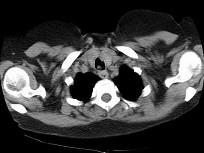

问题 男,68岁,呼吸困难、轻度吞咽困难3月余,请结合CT,选择最可能的诊断 ( )

选项 A.气管乳头状瘤 B.气管脓肿 C.气管炎性假瘤 D.食管癌 E.甲状腺癌

答案 A